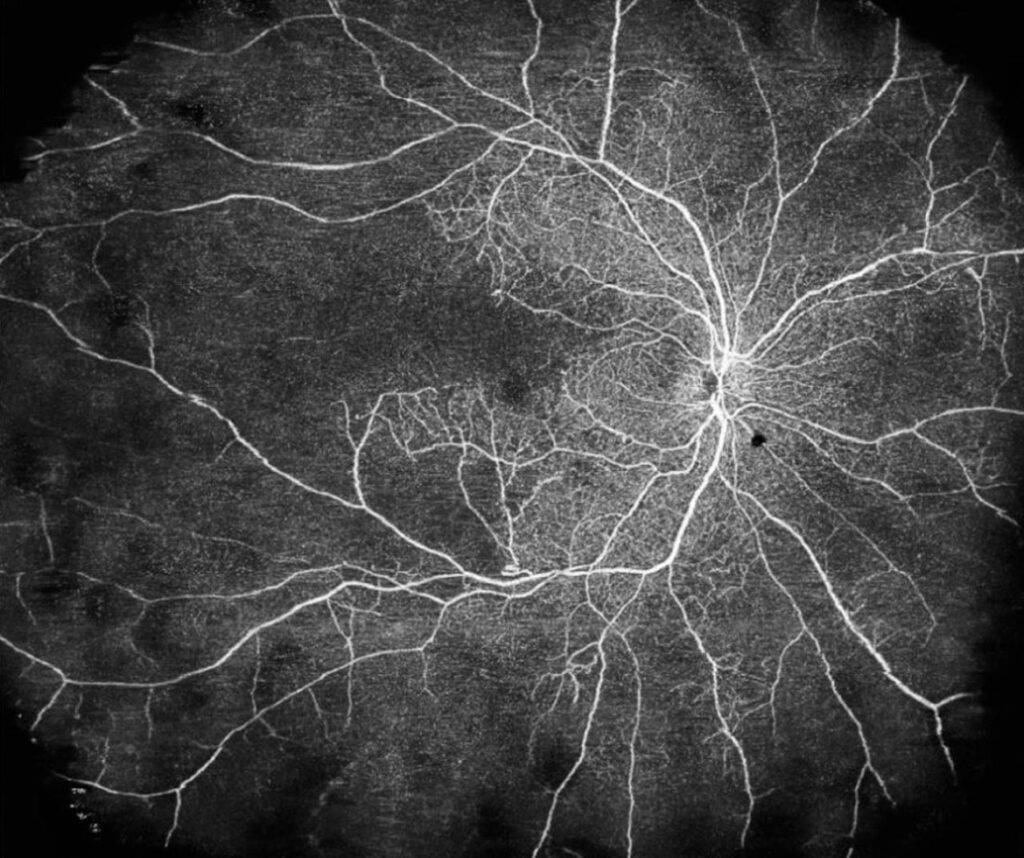

Fundusfotografie

Zusätzlich zur Funduskopie (oder manchmal auch an deren Stelle) kann der Augenarzt eine:n Assistent:in beauftragen, eine hochauflösende Weitwinkelfotografie des Augenhintergrunds zu machen. Ein Vorteil dieser Fundusfotografie ist, dass sie eine dauerhafte Aufzeichnung des Aussehens der Netzhaut und der Blutgefäße der Netzhaut am Tag der Untersuchung des diabetischen Auges erstellt.